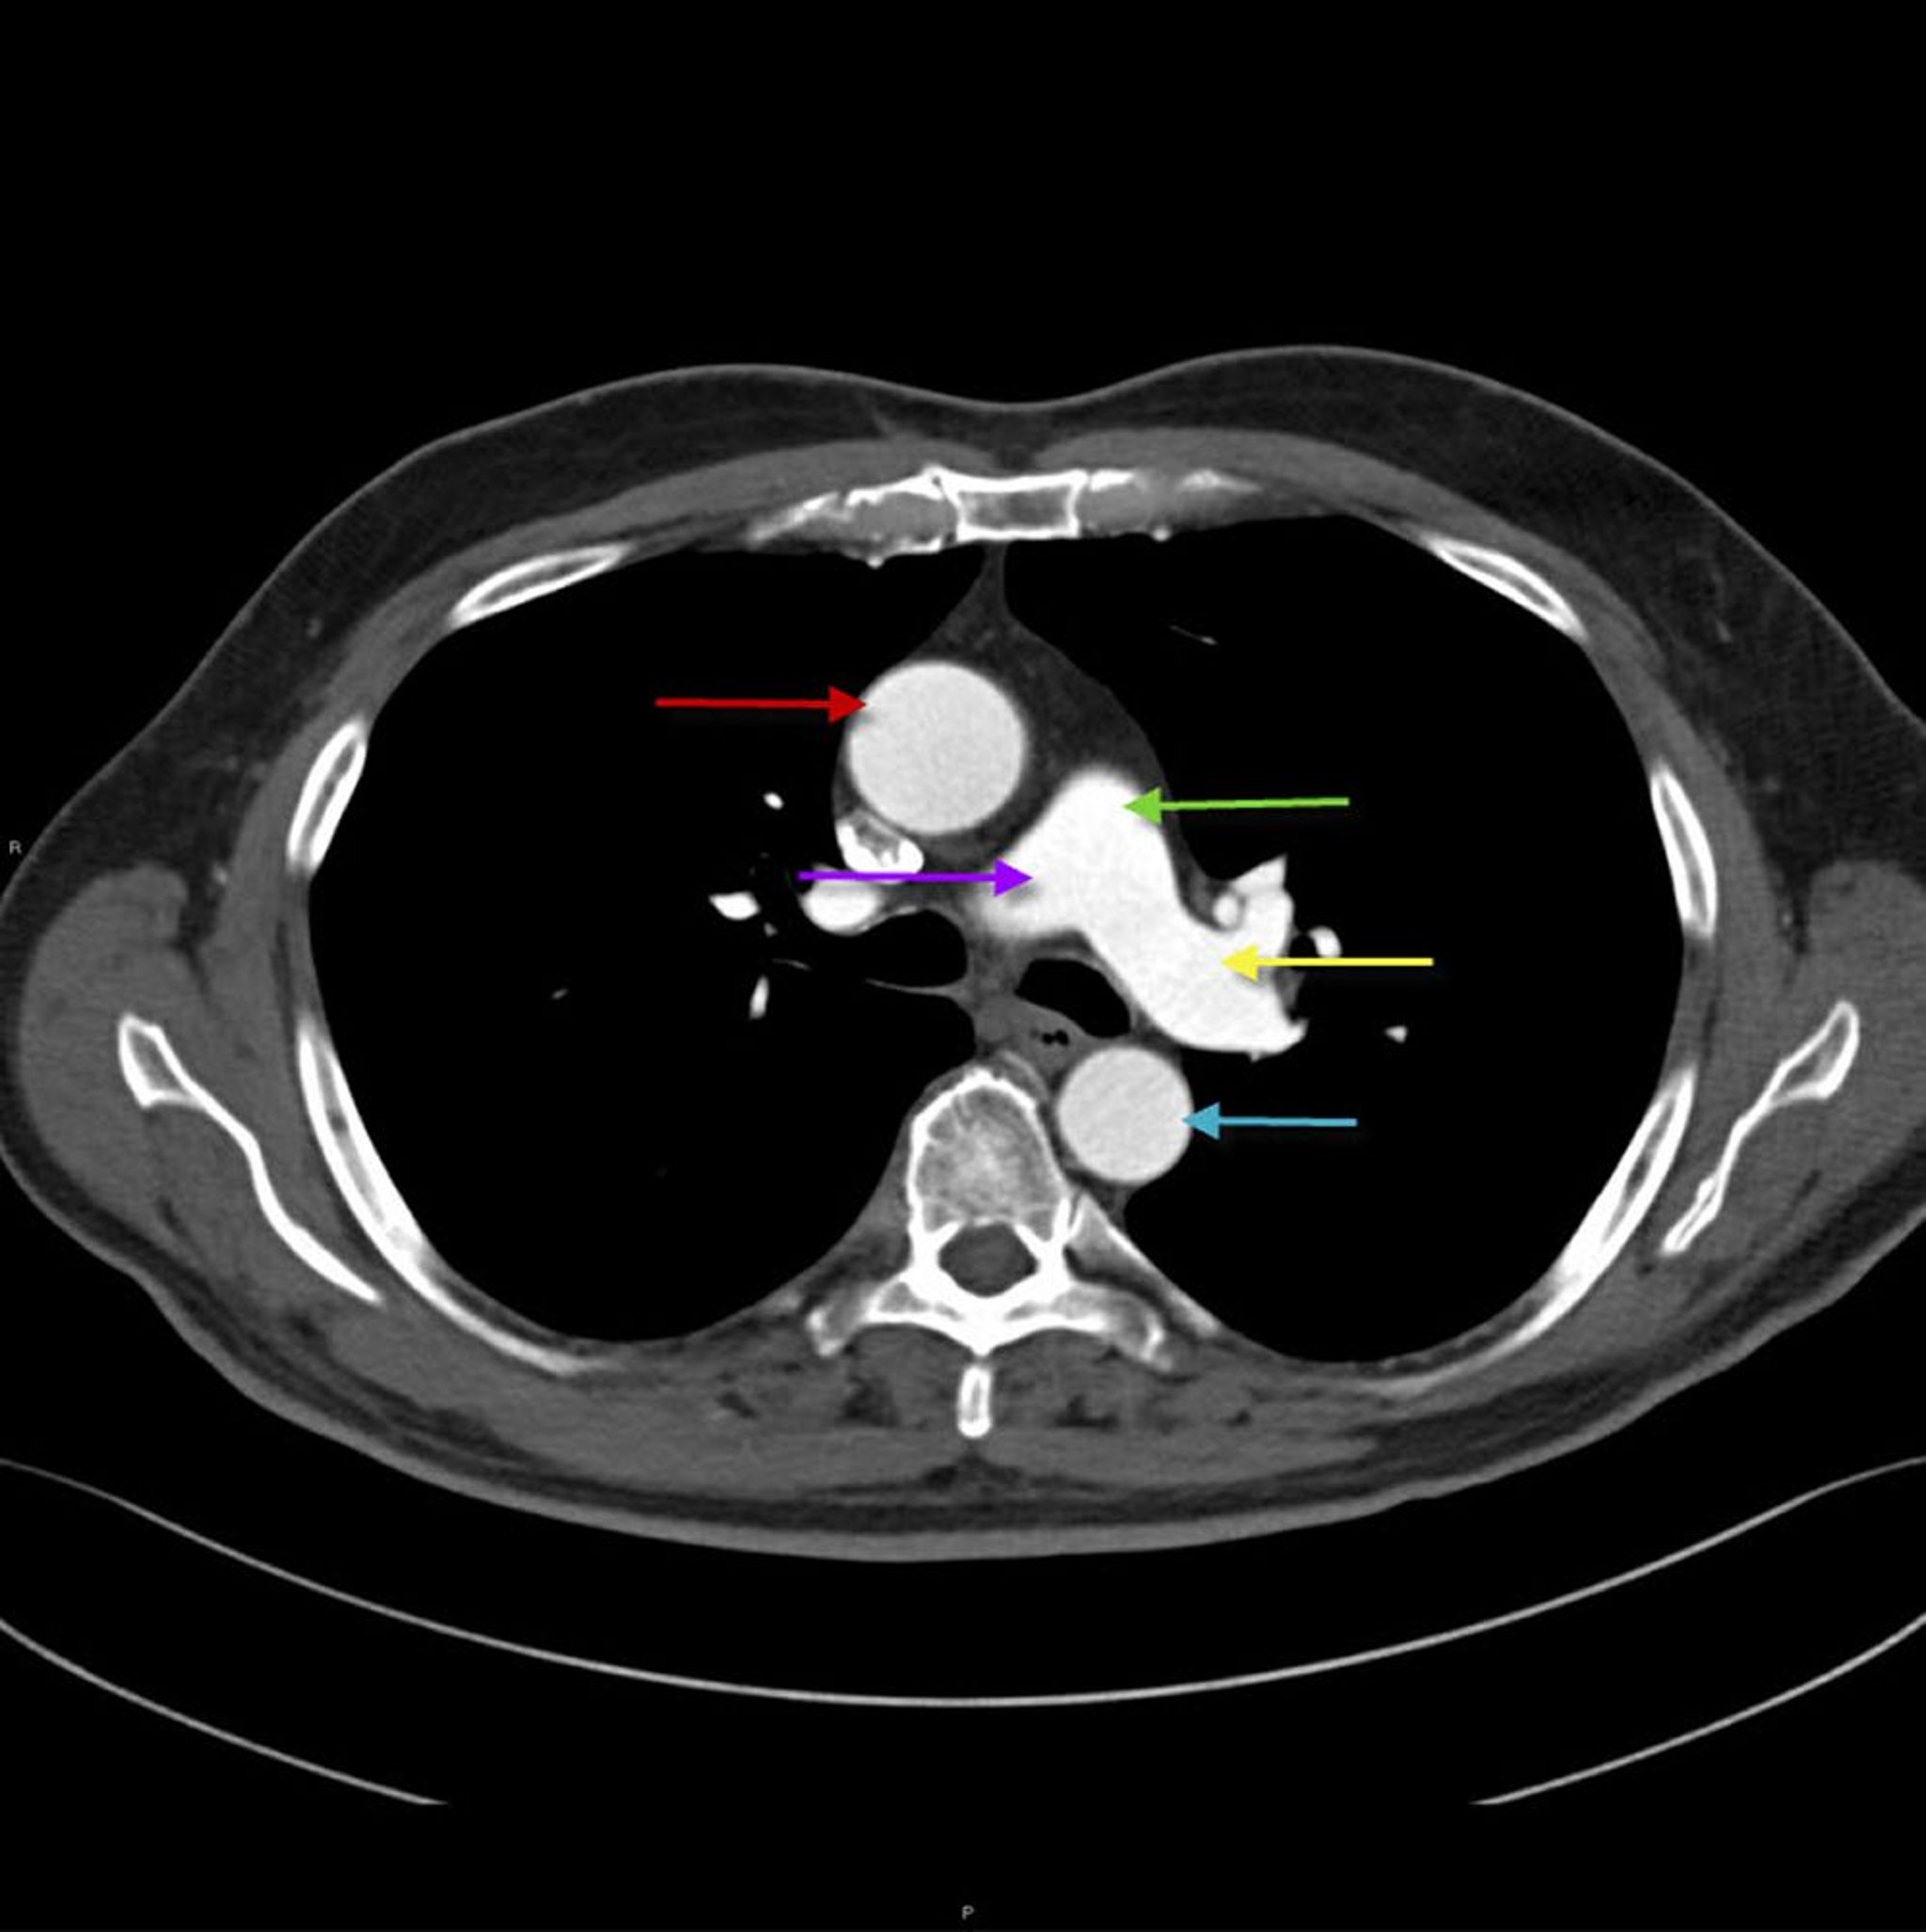

CT des Thorax mit Darstellung der Anatomie von Aorta und Pulmonalarterie

Dieses Bild zeigt die aufsteigende thorakale Aorta (roter Pfeil) mit absteigender thorakaler Aorta (blauer Pfeil). Die Hauptpulmonalarterie (grüner Pfeil) teilt sich in die rechte (lila Pfeil) und linke (gelber Pfeil) Pulmonalarterie.